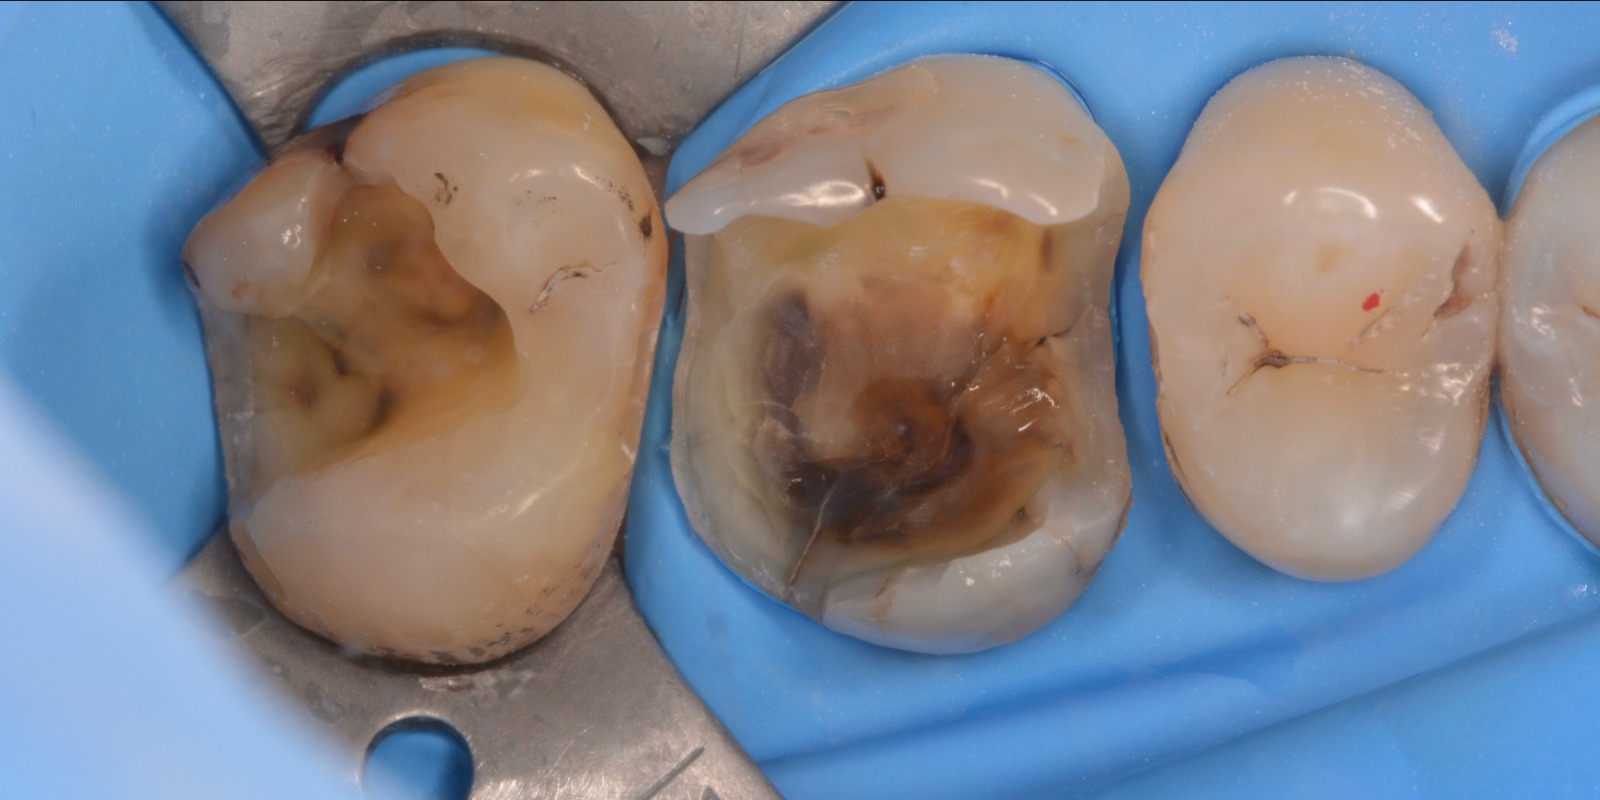

Tento kurz má jasný cíl - ukázat, že modelace okluzní plochy laterálních zubů nemusí být až taková věda, pokud známe správnou anatomii zubů a jejich funkci.

Podrobná anatomie všech laterálních zubů, pěkně jeden po druhém. Každý hrbolek, každý svah, každou fissuru, aproximální val a body kontaktu.